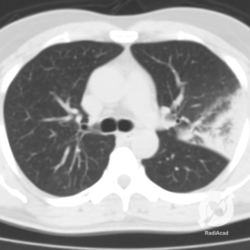

Os agentes etiológicos infecciosos são variados (bactérias, vírus, fungos, parasitas…), mas o que ocorre nos pulmões durante uma infecção por qualquer tipo de agente é a substituição do ar alveolar por secreção (pus, muco, eventualmente sangue ou necrose…) e com isso a manifestação radiográfica vai ser a mesma já que todas estas secreções apresentam a mesma densidade radiográfica: partes moles.

E o nome dado a esta alteração radiográfica que corresponde à substituição do ar alveolar por líquido é a consolidação alveolar.

Uma consolidação alveolar é, por definição, uma opacidade (imagem densa, branquinha) homogênea ou às vezes heterogênea (pela presença de calcificações ou cavidades), de limites mal definidos, exceto quando toca a pleura da parede ou das cissuras pulmonares. É um termo usado tanto em radiografia, como em tomografia computadorizada. Na tomografia, um outro termo é usado: vidro fosco, que é uma opacidade (branquinha mas não tanto como a consolidação), que borra o pulmão mas deixa ver os vasos de permeio (igual bigode de adolescente: dá pra ver todo o fundo).

Nós vamos mostrar aqui um pequeno apanhado de pneumonias de variados agentes, em diversos segmentos e lobos pulmonares, com extensões variadas. O objetivo é identificar o padrão radiológico de consolidação alveolar e não determinar o agente infeccioso, isso vai ser assunto para mais adiante. Aliás já antecipo que é fundamental saber localizar a lesão, porque alguns destes bichos gostam de determinados segmentos, alguns tumores também têm as suas preferências, então localização é fundamental. Se localização não fosse importante, um apartamento na beira do mar sairia o mesmo preço de um apartamento de frente pra BR-101, concordam?